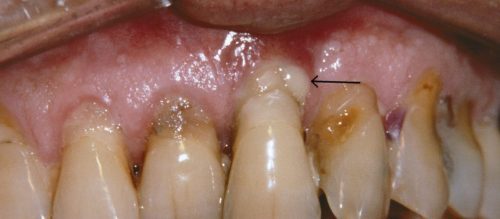

عفونت لثه دندان (Gum Infection) تحت تاثیر عوامل مختلفی مثل بیماریهای خاص، مصرف دارو، نقص سیستم ایمنی و…. ایجاد میشود و در صورتی که به موقع درمان نشود عفونت اولیه لثه یا ژنژیویت به مرحله شدید چرک لثه یعنی پریودنتیت تبدیل میشود که این اتفاق بسیار خطرناک است اما به کمک دندانپزشک متخصص پریو حرفهای قابل درمان است.

لثه های عفونی در مراحل اولیه ژنژیویت نام دارد که میتوان آن را با جرمگیری دندان و لثه کمک دندانپزشک متخصص حرفهای و توجه به رعایت نکات بهداشت دهان و دندان مثل استفاده منظم از مسواک، نخ دندان و دهانشویه و…. درمان کرد.

در صورتی که به ژنژیویت بیتوجه باشید و سریعا برای درمان آن اقدام نکنید عفونت اولیه لثه در زمان کوتاهی به بیماری پریودنتال لثه تبدیل میشود و پریودنتیت مرحله شدید و پیشرفته بیماری لثه است که درمان و بهبودی کامل آن بسیار سخت و زمانبرتر از درمان ژنژیویت است واگر به آن رسیدگی نشود منجر به از دست رفتن بافتها و استخوان پشتیبان دندان و تحلیل استخوان فک میشود.